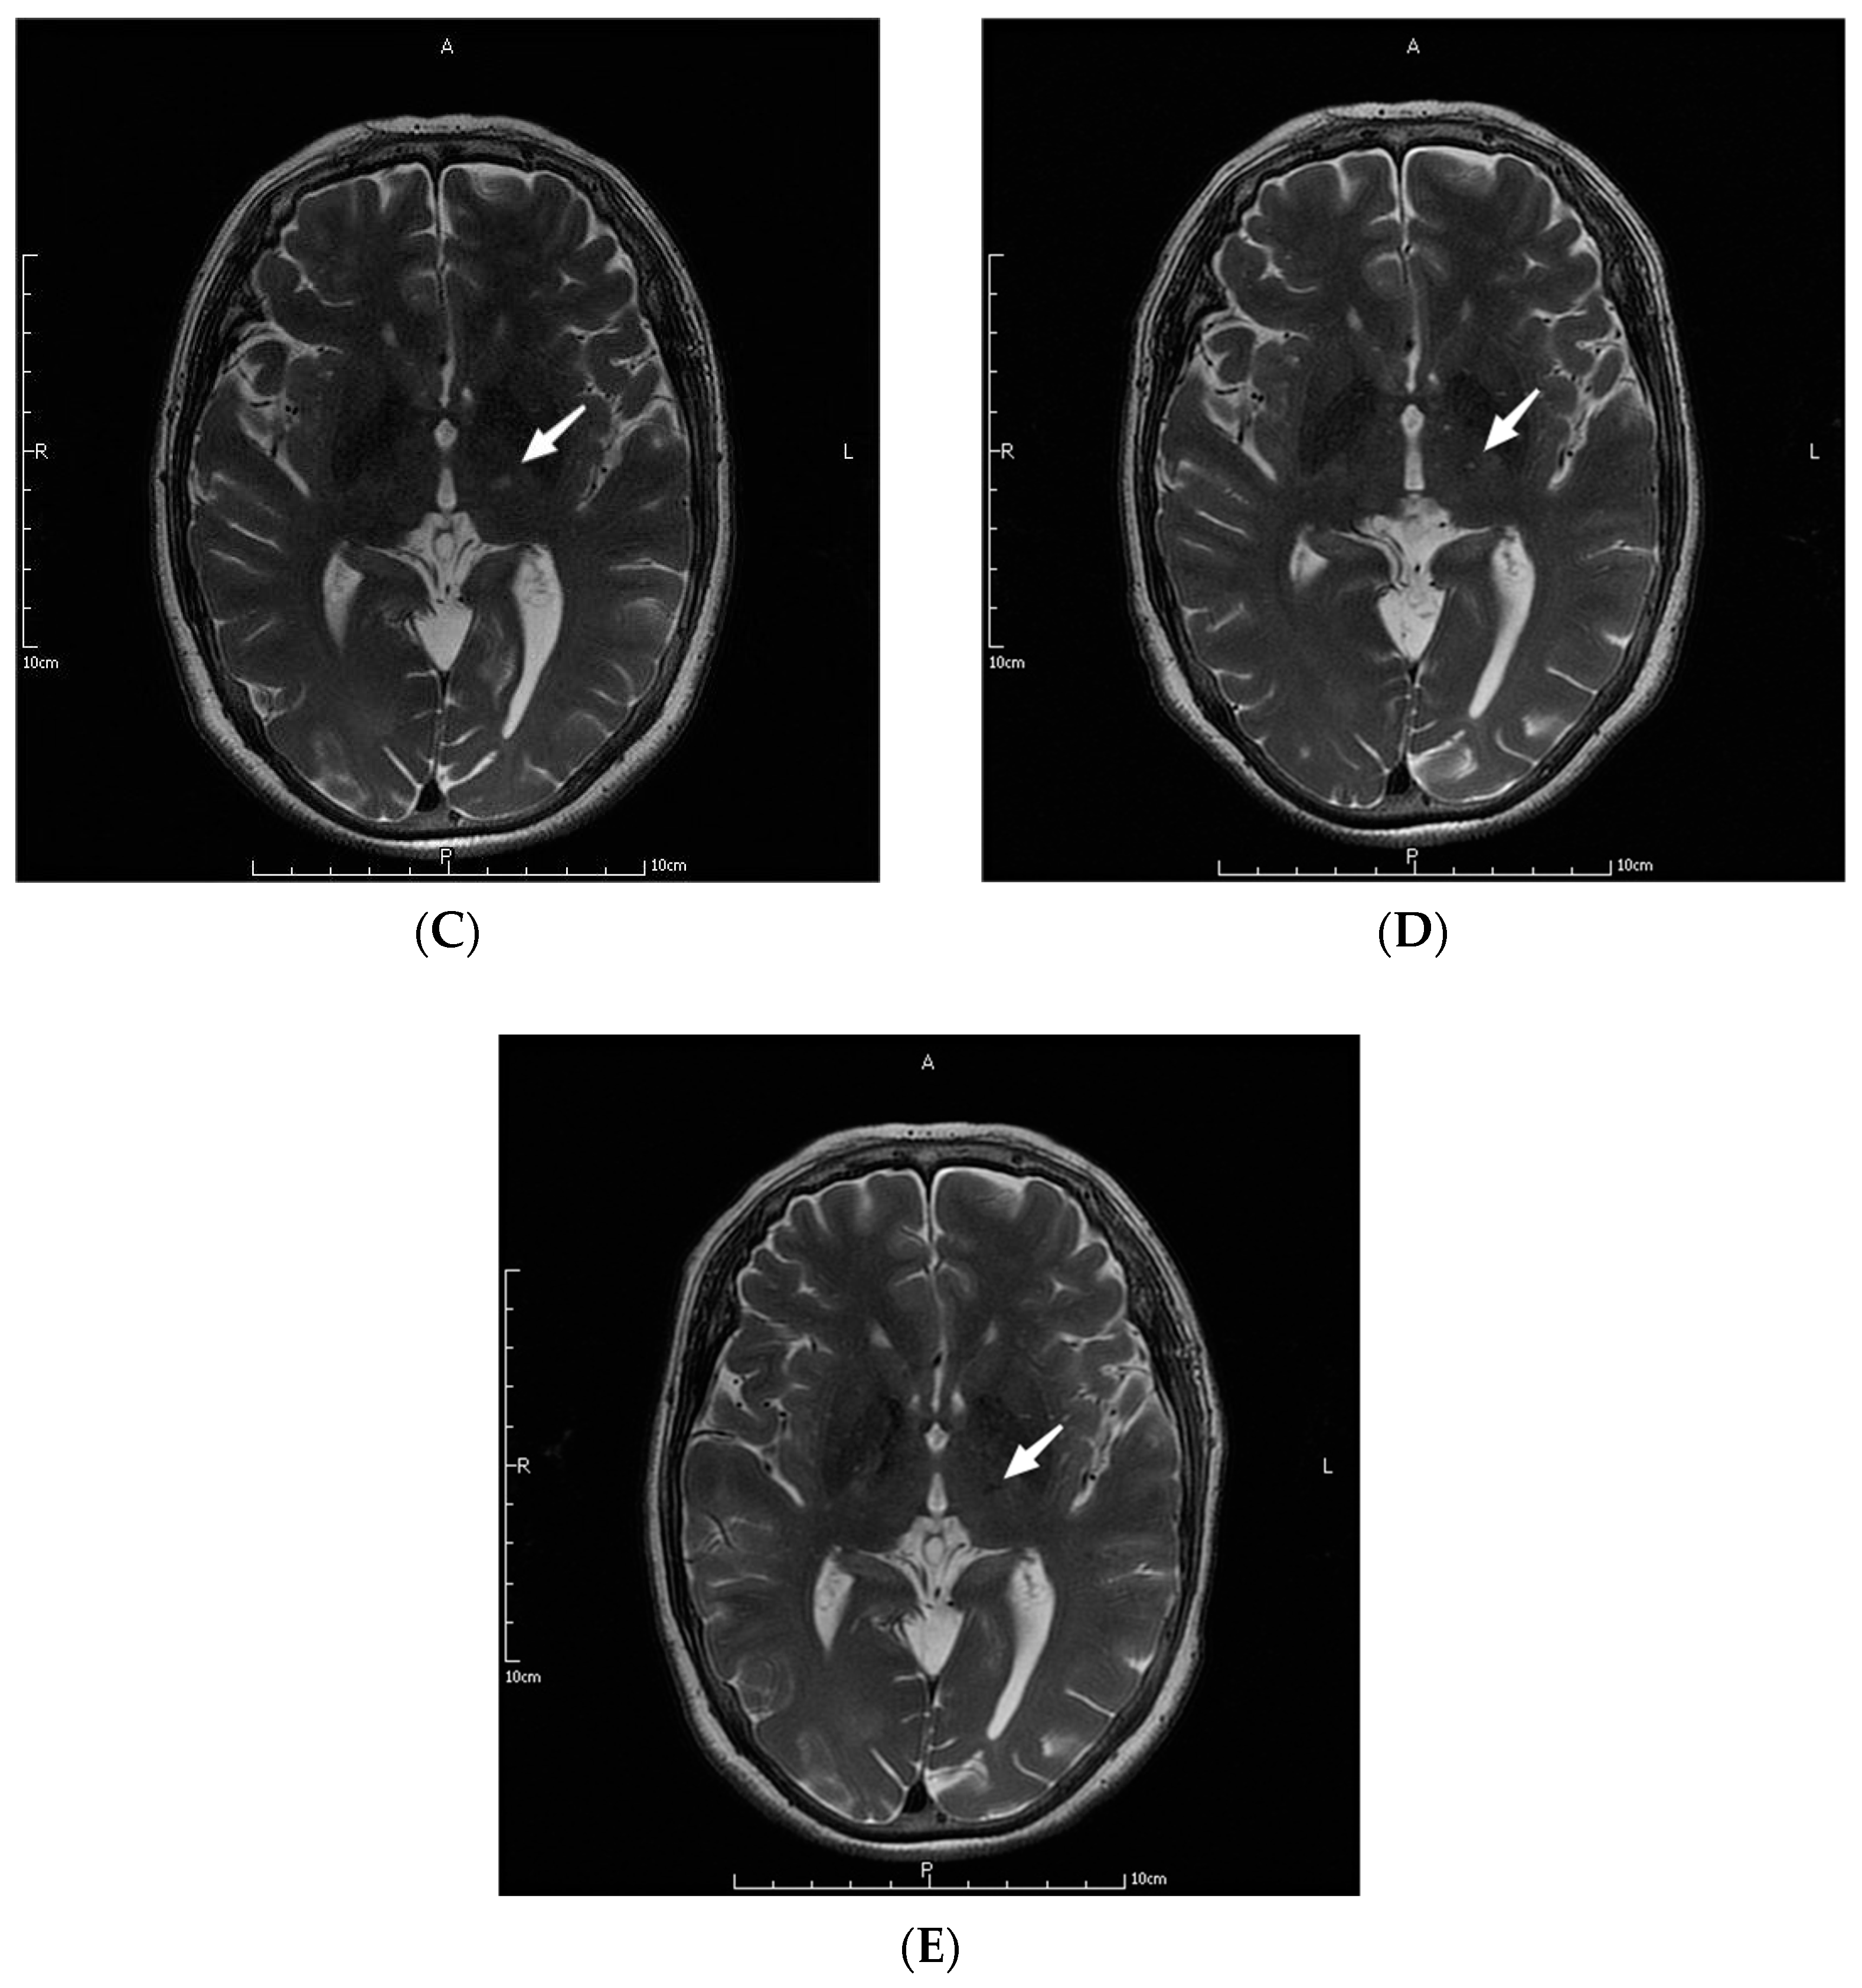

The parameters in the MRgFUS surgery were as follows: the mean ablation time of the 9 patients was 6.22 ± 2.64 s, and the average maximum temperature was 57.89 ± 1.36 °C. Figure 1 shows the MRI images of the patient No. 3 before, during, and at one month, three months, and one year after the operation.

MRI images of a patient before (A), during (B), and at one month (C), three months (D), and one year (E) after the operation. The letters in the pictures are abbreviations of anterior (A), posterior (P), left (L) and right (R). The white arrow pointed to the lesions created by MRgFUS Vim ablation.